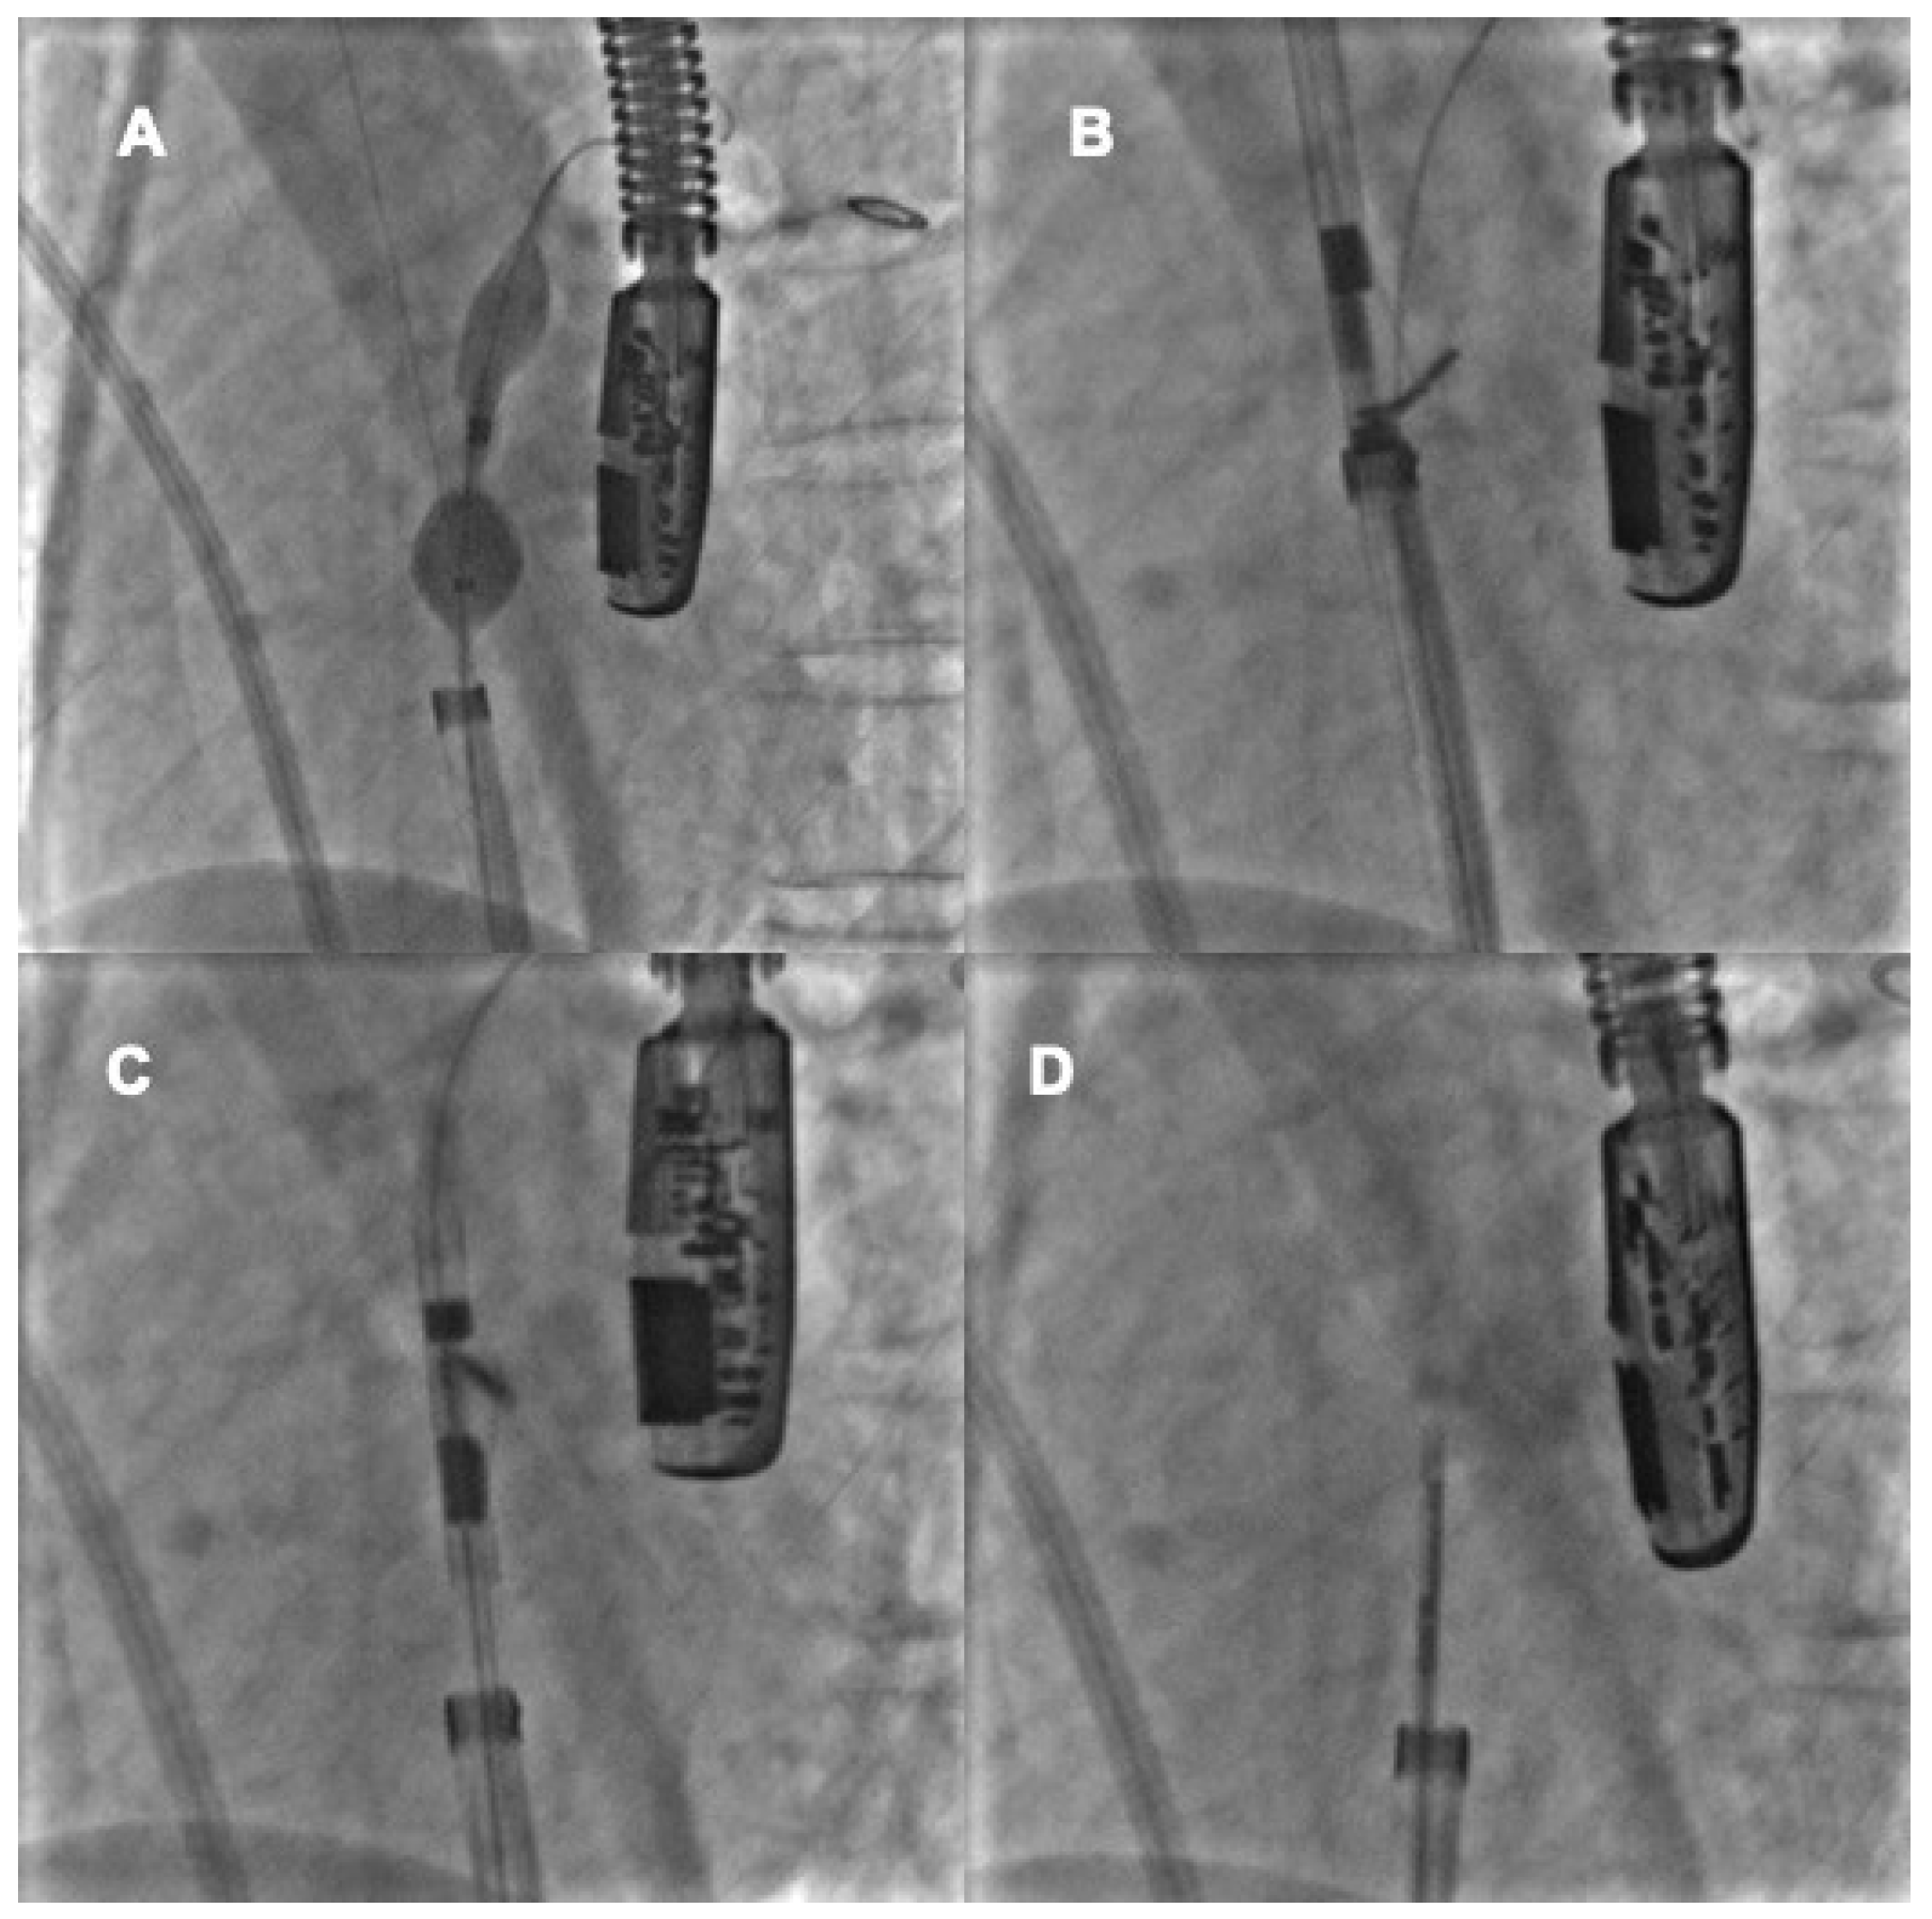

4. Percutaneous Closure of PFO by Novel Devices: The NobleStitch

4.1. Procedural Steps

4.2. Role of TEE